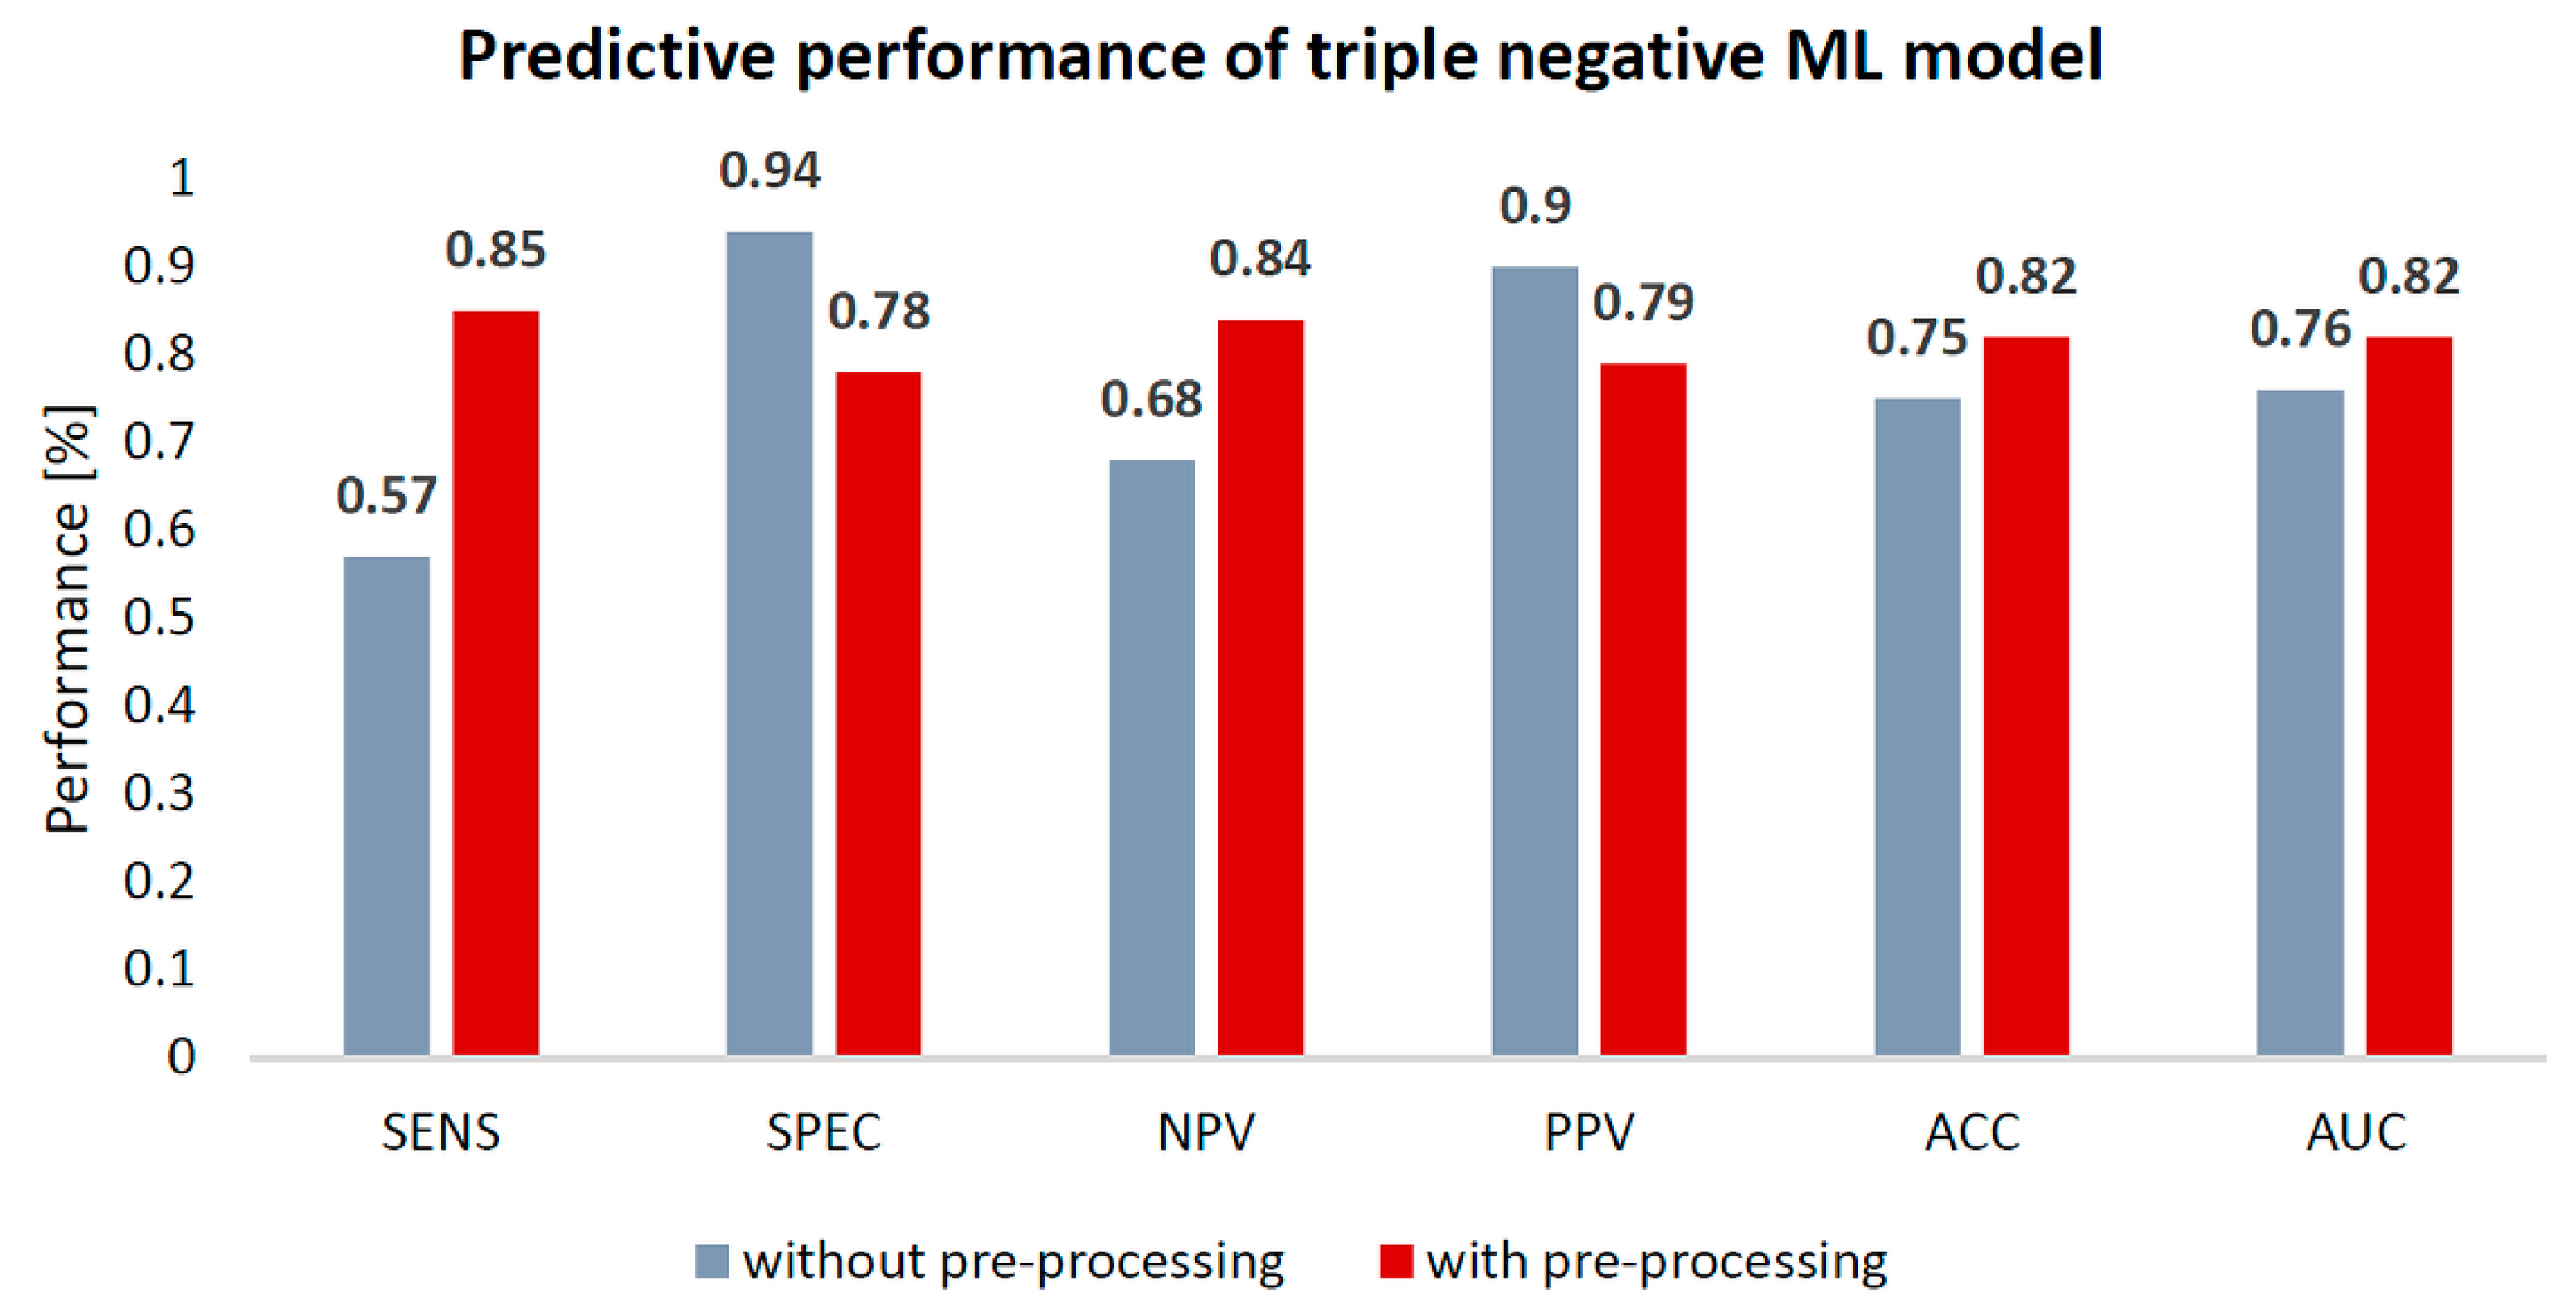

3.2.2. Breast Cancer Subtyping

| Model | Data Preprocessing | SENS | SPEC | NPV | PPV | ACC | AUC |

| Triple negative | No | 57 | 94 | 68 | 90 | 75 | 0.76 |

| Yes | 85↑ | 78 | 84↑ | 79 | 82↑ | 0.82↑ | |